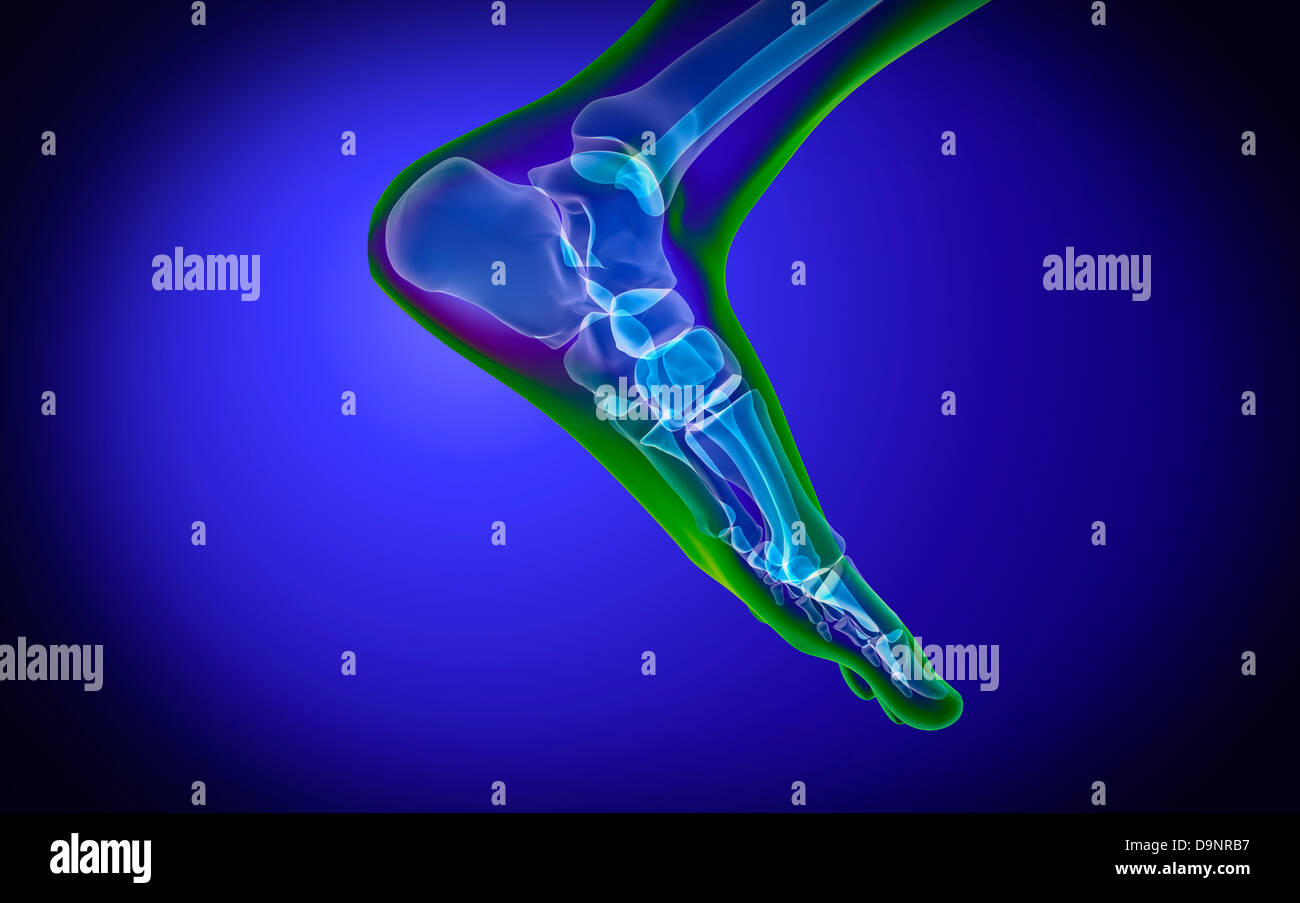

RF2R3WKY1–Illustration médicale des principales parties des os du pied en vue latérale, avec annotations.